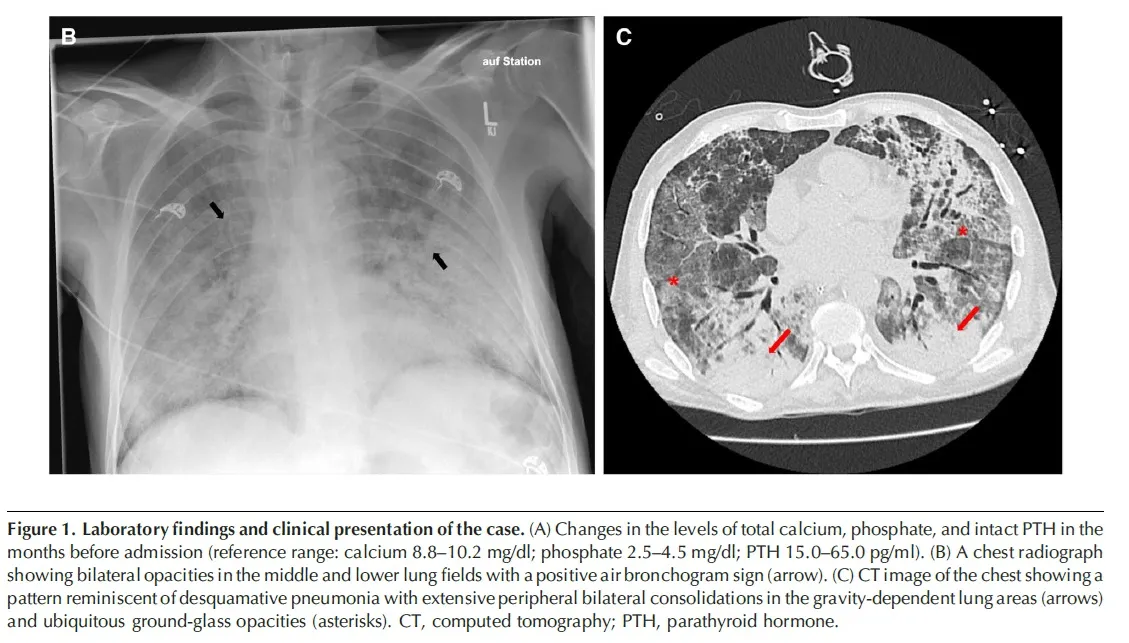

Hipercalcemia e Febre em transplantado Renal